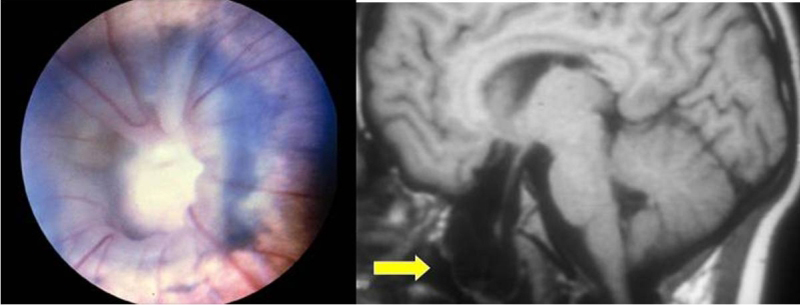

- Defectos quiasmáticos. El defecto típico de lesión quiasmática es una hemianopsia bitemporal heterónima. Si ésta es de predominio superior, la sospecha corresponde a lesiones que comprimen el quiasma desde abajo (ej. adenoma de hipófisis), y si es inferior, a lesiones supraquiasmáticas (ej. craneofaringioma), sin olvidar la posibilidad de quiasmopatías intrínsecas (tumorales o inflamatorias). En casos de larga evolución puede observarse la atrofia en banda o en pajarita en ambos discos ópticos. Si la hemianopsia se presenta de manera súbita, acompañada de cefalea intensa y/o náuseas y vómitos, u oftalmoparesia hay que descartar la apoplejía o ictus hipofisario. Se debe realizar una RM o TC craneal urgente ya que este proceso requiere tratamiento quirúgico inmediato (Figura 12).

Figura 12. Apoplejía hipofisiaria. Nivel de hiper/hipointensidad provocado por sangrado agudo (cuando el paciente está en decúbito)